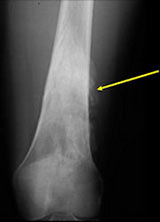

- There may be invasion of the medullary canal with long standing disease

- Useful for determining medullary invasion

- Metastases more common with medullary invasion, high grade components (grade 3) and dedifferentiation (grade 3 tumors)

- Many parosteal osteosarcomas with intramedullary extension are higher grade lesions or dedifferentiated tumors